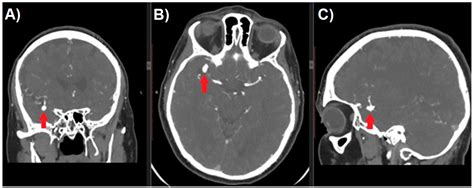

A computed tomography (CT) scan is a non-invasive diagnostic tool that uses X-rays and computer processing to create detailed cross-sectional images of your brain. When a physician orders a Cat Scan brain aneurysm screening, they are looking for specific indicators of blood vessel distress. In many emergency scenarios, such as the sudden onset of a “thunderclap” headache, a non-contrast CT scan is the first line of defense to rule out acute bleeding, known as a subarachnoid hemorrhage.

While a standard CT scan is excellent for identifying active bleeding, a CT Angiography (CTA) is typically required to visualize the actual anatomy of the aneurysm. By injecting a contrast dye into the bloodstream, radiologists can map the arteries of the brain with high precision. This allows them to see the size, shape, and exact location of a potential aneurysm, which is essential for determining the best course of treatment.

Once the scan is complete, a radiologist analyzes the images to look for any abnormalities in the cerebral vasculature. If an aneurysm is identified, the report will detail its size and morphology. Smaller aneurysms are often managed through “watchful waiting” and strict blood pressure control, whereas larger or more complex aneurysms may require surgical intervention, such as clipping or endovascular coiling.